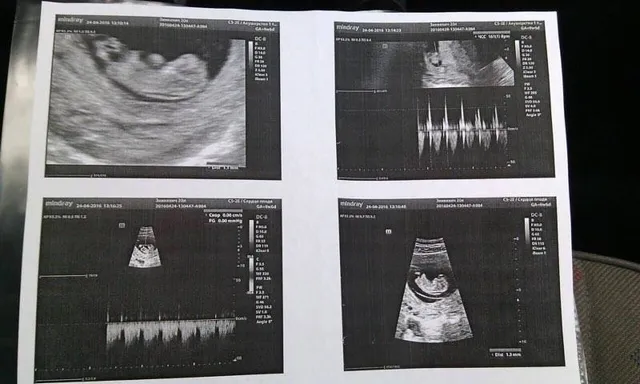

Я забеременела почти сразу после ДТП, примерно через месяц. В принципе это по природе вообще невозможно, это довольно странно, потому что по прогнозам я не могла стать матерью. Но случилось, как случилось,

— рассказала девушка во время пресс-конференции, показав снимки УЗИ.

На пресс-конференции она сообщила, что ждет первенца ориентировочно в октябре, передает корреспондент 24 Канала Алевтина Варава.